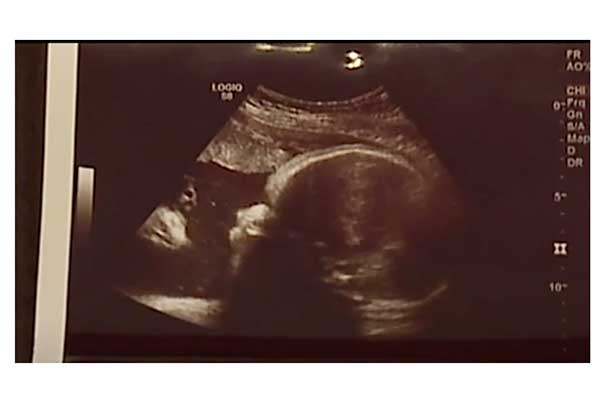

妊婦健診 4dエコーでついに赤ちゃんの顔が 妊娠35週2400g 京都府宮津市 理美容室 Ddy Hair イッチー 市田智大 の毎日ブログ

今 26w6dの7ヶ月の妊婦です 4dエコーで初めて赤ちゃんの顔が見え Yahoo 知恵袋

4dエコー ハーフ

妊娠25週の胎児 エコー動画と4dエコー動画 Youtube